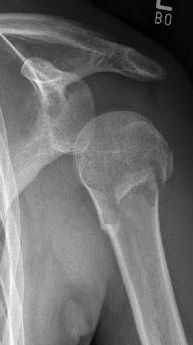

Proximaler Oberarmbruch9Proximaler Oberarmbruch10

Picture: A subcapital upper arm fracture was treated with a prosthesis. The humeral head was completely removed and replaced by the prosthesis. This is anchored in the upper arm with the prosthesis shaft.